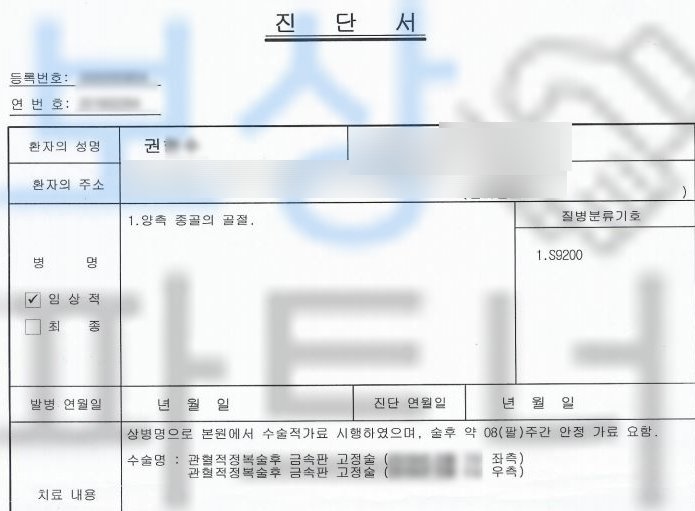

진단서를 보시면

양 발의 종골(calcaneus) 골절

S9200 진단을 받으셨습니다. 먼저 일하시다 재해를 당하셨다면 의무 보험인 산재 보험에서 요양급여, 휴업급여, 장해급여까지 보상 가능하십니다. 의뢰인의 경우 이미 산재처리를 하여 저희 보상 파트너에서는 고객님께서 개인적으로 가입하신 보험 증권을 확인했고

급수 보험도 있으셨습니다. 저희는 올바르고 분명한 보험금을 위해 공신력 있는 대학병원의 전문의로부터 후유 장해 진단을 받았고, 그 결과

권@@님은 무려 AMA 약관상

좌측은 뚜렷한 기능 장해 10%

우측은 약간의 기능 장해 5%

생명보험약관상은

우측은 장해에 해당이 안 되고

좌측은 뚜렷한 장해 6급에

해당되었습니다.